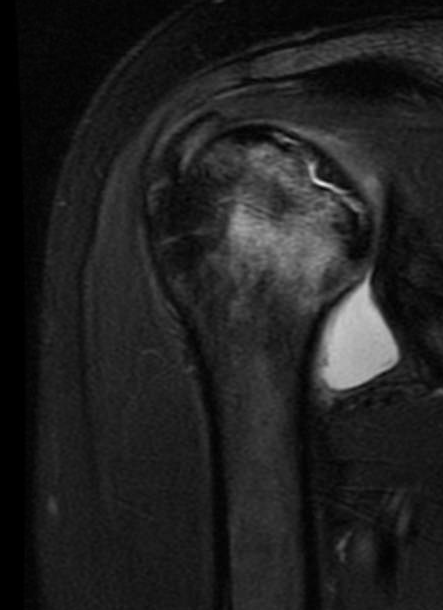

and her MRI revealed the diagnosis of avascular necrosis with a crack below the joint surface of the humeral head.

and this MRI